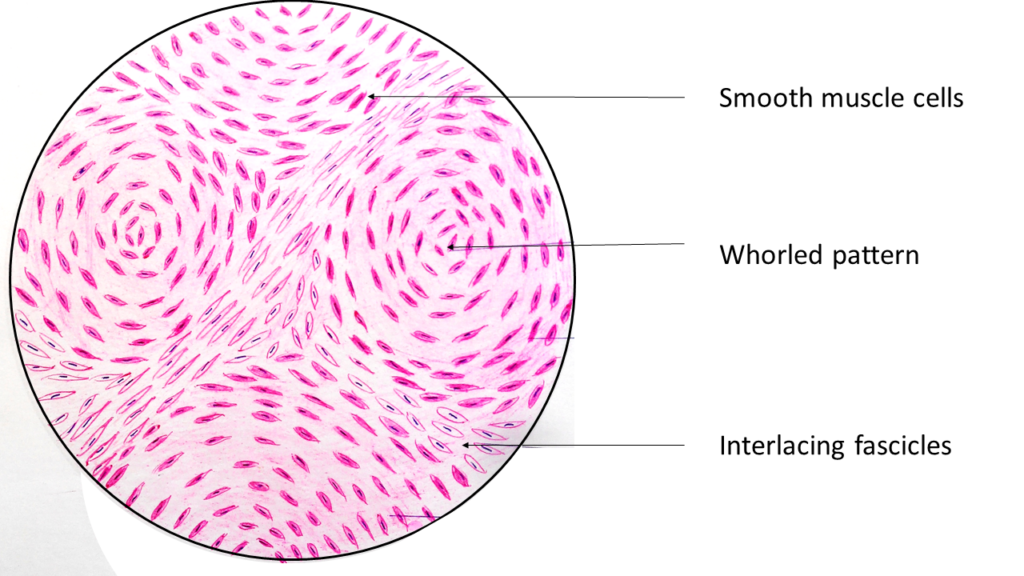

Uterine Leiomyoma At 10x Magnification | Nikon’s MicroscopyU

www.microscopyu.com

www.microscopyu.com

leiomyoma uterine 10x magnification leiomyomas pathology microscopyu symptoms

www.youtube.com

www.youtube.com

leiomyoma uterus histopathology

Uterine Leiomyoma - Libre Pathology

librepathology.org

librepathology.org